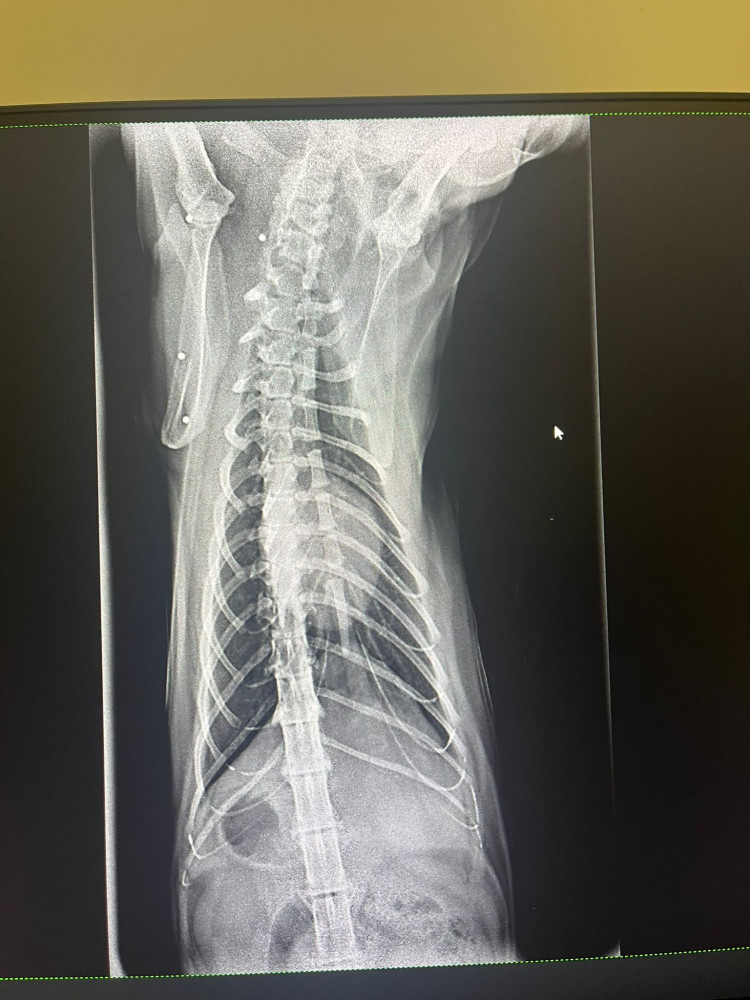

Lo rescatamos desde Francia, y, al llegar aquí, nos encontramos con este panorama desolador para él:  una auténtica barbaridad de perdigones en el cuerpo y una cardiopatía ❤️‍🩹 Las imágenes hablan por sí solas...